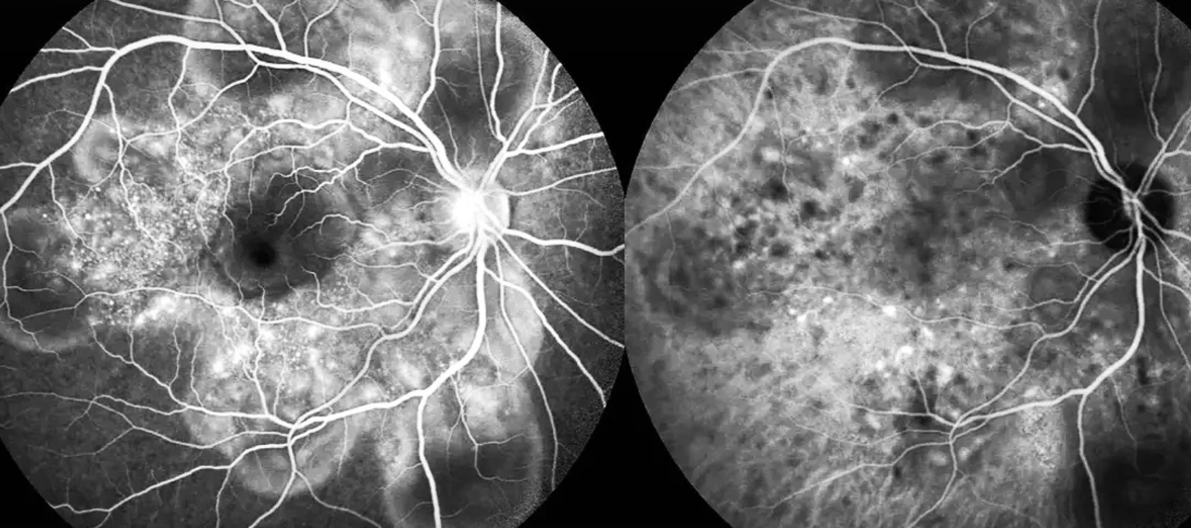

- Juara 1 dalam kategori Angiografi Hijau Indosianin, untuk foto berjudul “Penyakit Vogt-Koyanagi-Harada”

- Juara 2 dalam kategori Tomografi Koherensi Optik, untuk foto berjudul “Penyakit Vogt-Koyanagi-Harada”